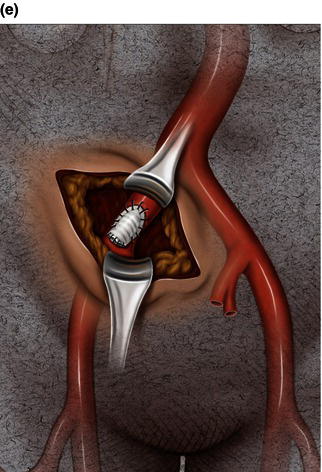

A 15 cm semi-lunar right flank incision is made four finger-breaths above the groin crease. Division of the external oblique, internal oblique and transversus abdominus muscles is performed in the direction of their fibers. The extraperitoneal fascia and peritoneum are then retracted medially and dissection is carried out in the avascular plane of the retroperitoneum down to the level of the psoas muscle. All of the abdominal contents are then retracted medially with the help of a handheld retractor or an Omni retractor, providing excellent exposure of the lower infrarenal aorta, common iliac artery, and iliac bifurcation. The right common iliac artery along with the hypogastric and the external iliac artery are identified and mobilized (Fig. 1.14a). Care is taken to spare the right urether which crosses the common iliac artery before diving deep into the pelvis. A Rummel tourniquet is applied to control the proximal common iliac artery, the external iliac artery, and origin of the hypogastric artery; alternatively, vascular clamps could be applied for control. Heparin is usually given to the patient prior to clamping the vessels. An arteriotomy is made on the common iliac artery with a no. 11 blade and extended with Pott’s scissors close to the bifurcation of the hypogastric artery and the external iliac artery. A 10 mm conduit is then sewn in an end-to-side fashion using 5-0 prolene sutures (Fig. 1.14b). The 10 mm graft is subsequently tunneled through the retroperitoneal space beneath the inguinal ligament and brought out through the groin incision used to expose the common femoral artery. The graft is subsequently flashed and clamped at the groin incision with the Rummel tourniquets released from the common iliac artery, external iliac artery, and hypogastric artery. The 10 mm conduit is subsequently looped with a Rummel tourniquet and ready to be punctured with an 18 gauge needle for access and introduction of a guide wire and an introducer sheath (Fig. 1.14c). The introducer sheath is subsequently exchanged for a device sheath, which is advanced into the distal aorta (Fig. 1.14d). The endoluminal graft is then introduced into the delivery sheath and deployed to the target area. Wires and sheaths are removed from the 10 mm conduit and the conduit is clamped.

The conduit can either be trimmed to the appropriate length and the conduit tied off as a stump (Fig. 1.14e) or the distal end of the conduit can be sewn to the more distal iliac system in an end-to-end fashion as an interposition graft. Or, more commonly, the conduit can be brought to the groin by tunneling the conduit under the inguinal ligament and performing either an end-to-end anastomosis or an ilio-femoral conduit. The ilio-femoral conduit is performed by making an arteriotomy on the adequately exposed common femoral artery after adequate proximal and distal control is achieved. An end-to-side anastomosis is constructed with a 5-0 prolene suture with adequate flushing maneuvers performed prior to completion of the anastomosis (Fig. 1.14f). The ilio-femoral conduit is best for patients who may require further intervention for diffuse thoracic aneurysmal disease as the conduit may be reused through a simple infrainguinal incision in the future. The groin incision is approximated in layers. The right flank incision is irrigated, a 10 Fr Jackson–Pratt drain is placed in the retroperitoneal space and the incision closed in layers. The same technique can be applied to the infrarenal aorta and thoracic aorta. Similarly, end-to-side grafting of a conduit to the axillary artery, as described elsewhere, to facilitate deep hypothermic circulatory arrest also provides excellent access to the thoracic aorta via the innominate [2].

Fig. 1.14 (a) Retroperitoneal exposure. (b) A 10 mm conduit sewn to the iliac artery. (c) Conduit brought out of the incision with cannulation of the conduit with an introducer sheath. (d) Introducer sheath exchanged for a device sheath and advanced through the 10 mm conduit to the distal abdominal aorta. (e) Ligation of a 10 mm conduit. (f) Conduit tunneled and sewn to the femoral artery as an ilio-femoral conduit.